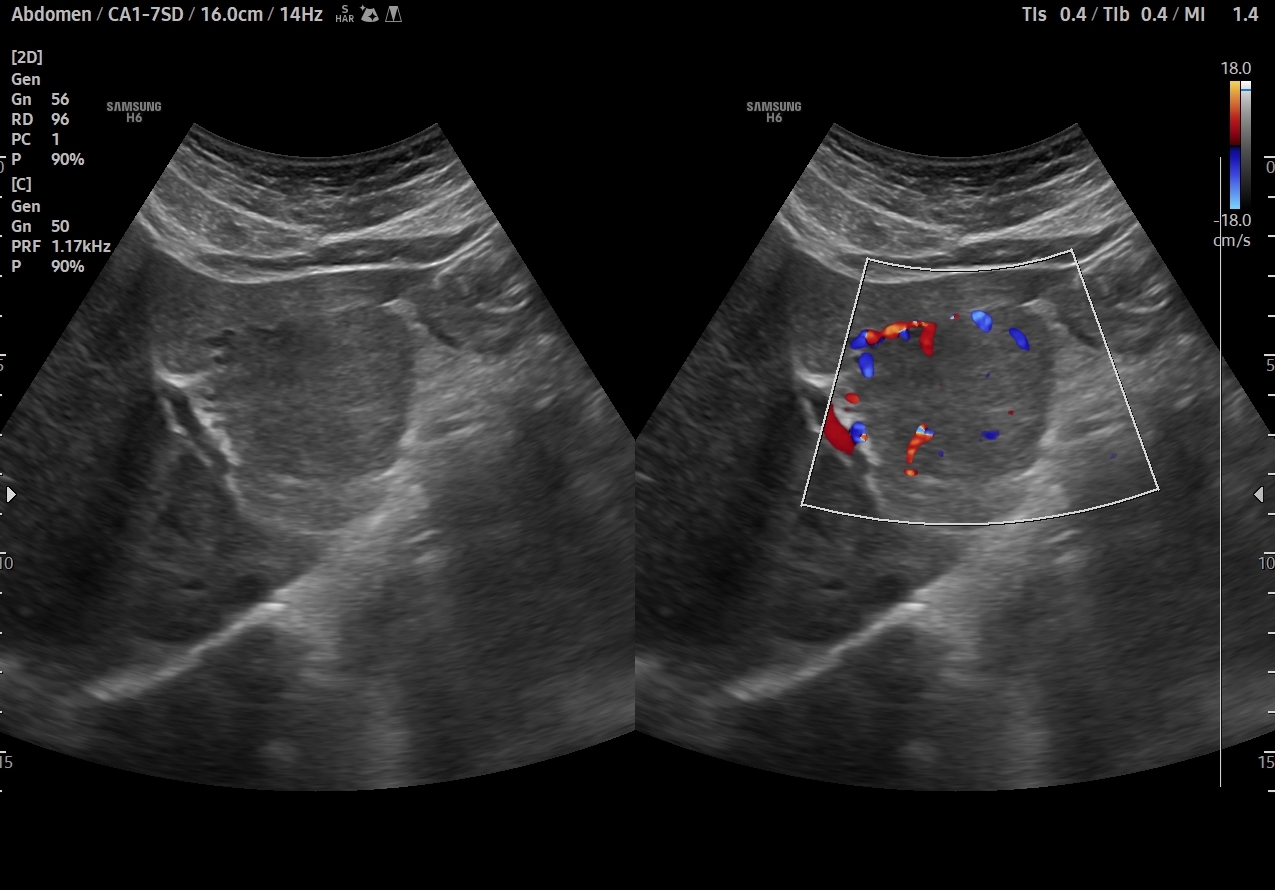

En el lóbulo hepático izquierdo visualizamos lesión focal iso-hipoecogénica respecto al parénquima hepático circundante que mide 4,6 x 4,5 x 3,9 cm y que presenta un aumento de la señal Doppler. Vemos la imagen tanto en cortes transversales como en cortes longitudinales, también con el modo Doppler activo. Resto de parénquima hepático y vía biliar de aspecto normal, sin otras alteraciones.

Dados los antecedentes de la paciente (edad y toma anticonceptivos orales) la imagen ecográfica inicial impresiona de hiperplasia nodular focal. El diagnóstico diferencial comprende otras lesiones focales en el hígado: hemangioma, adenoma, quiste, hepatocarcinoma, tumores metastásicos. En este caso la concordancia con la posterior RM hepática es total.